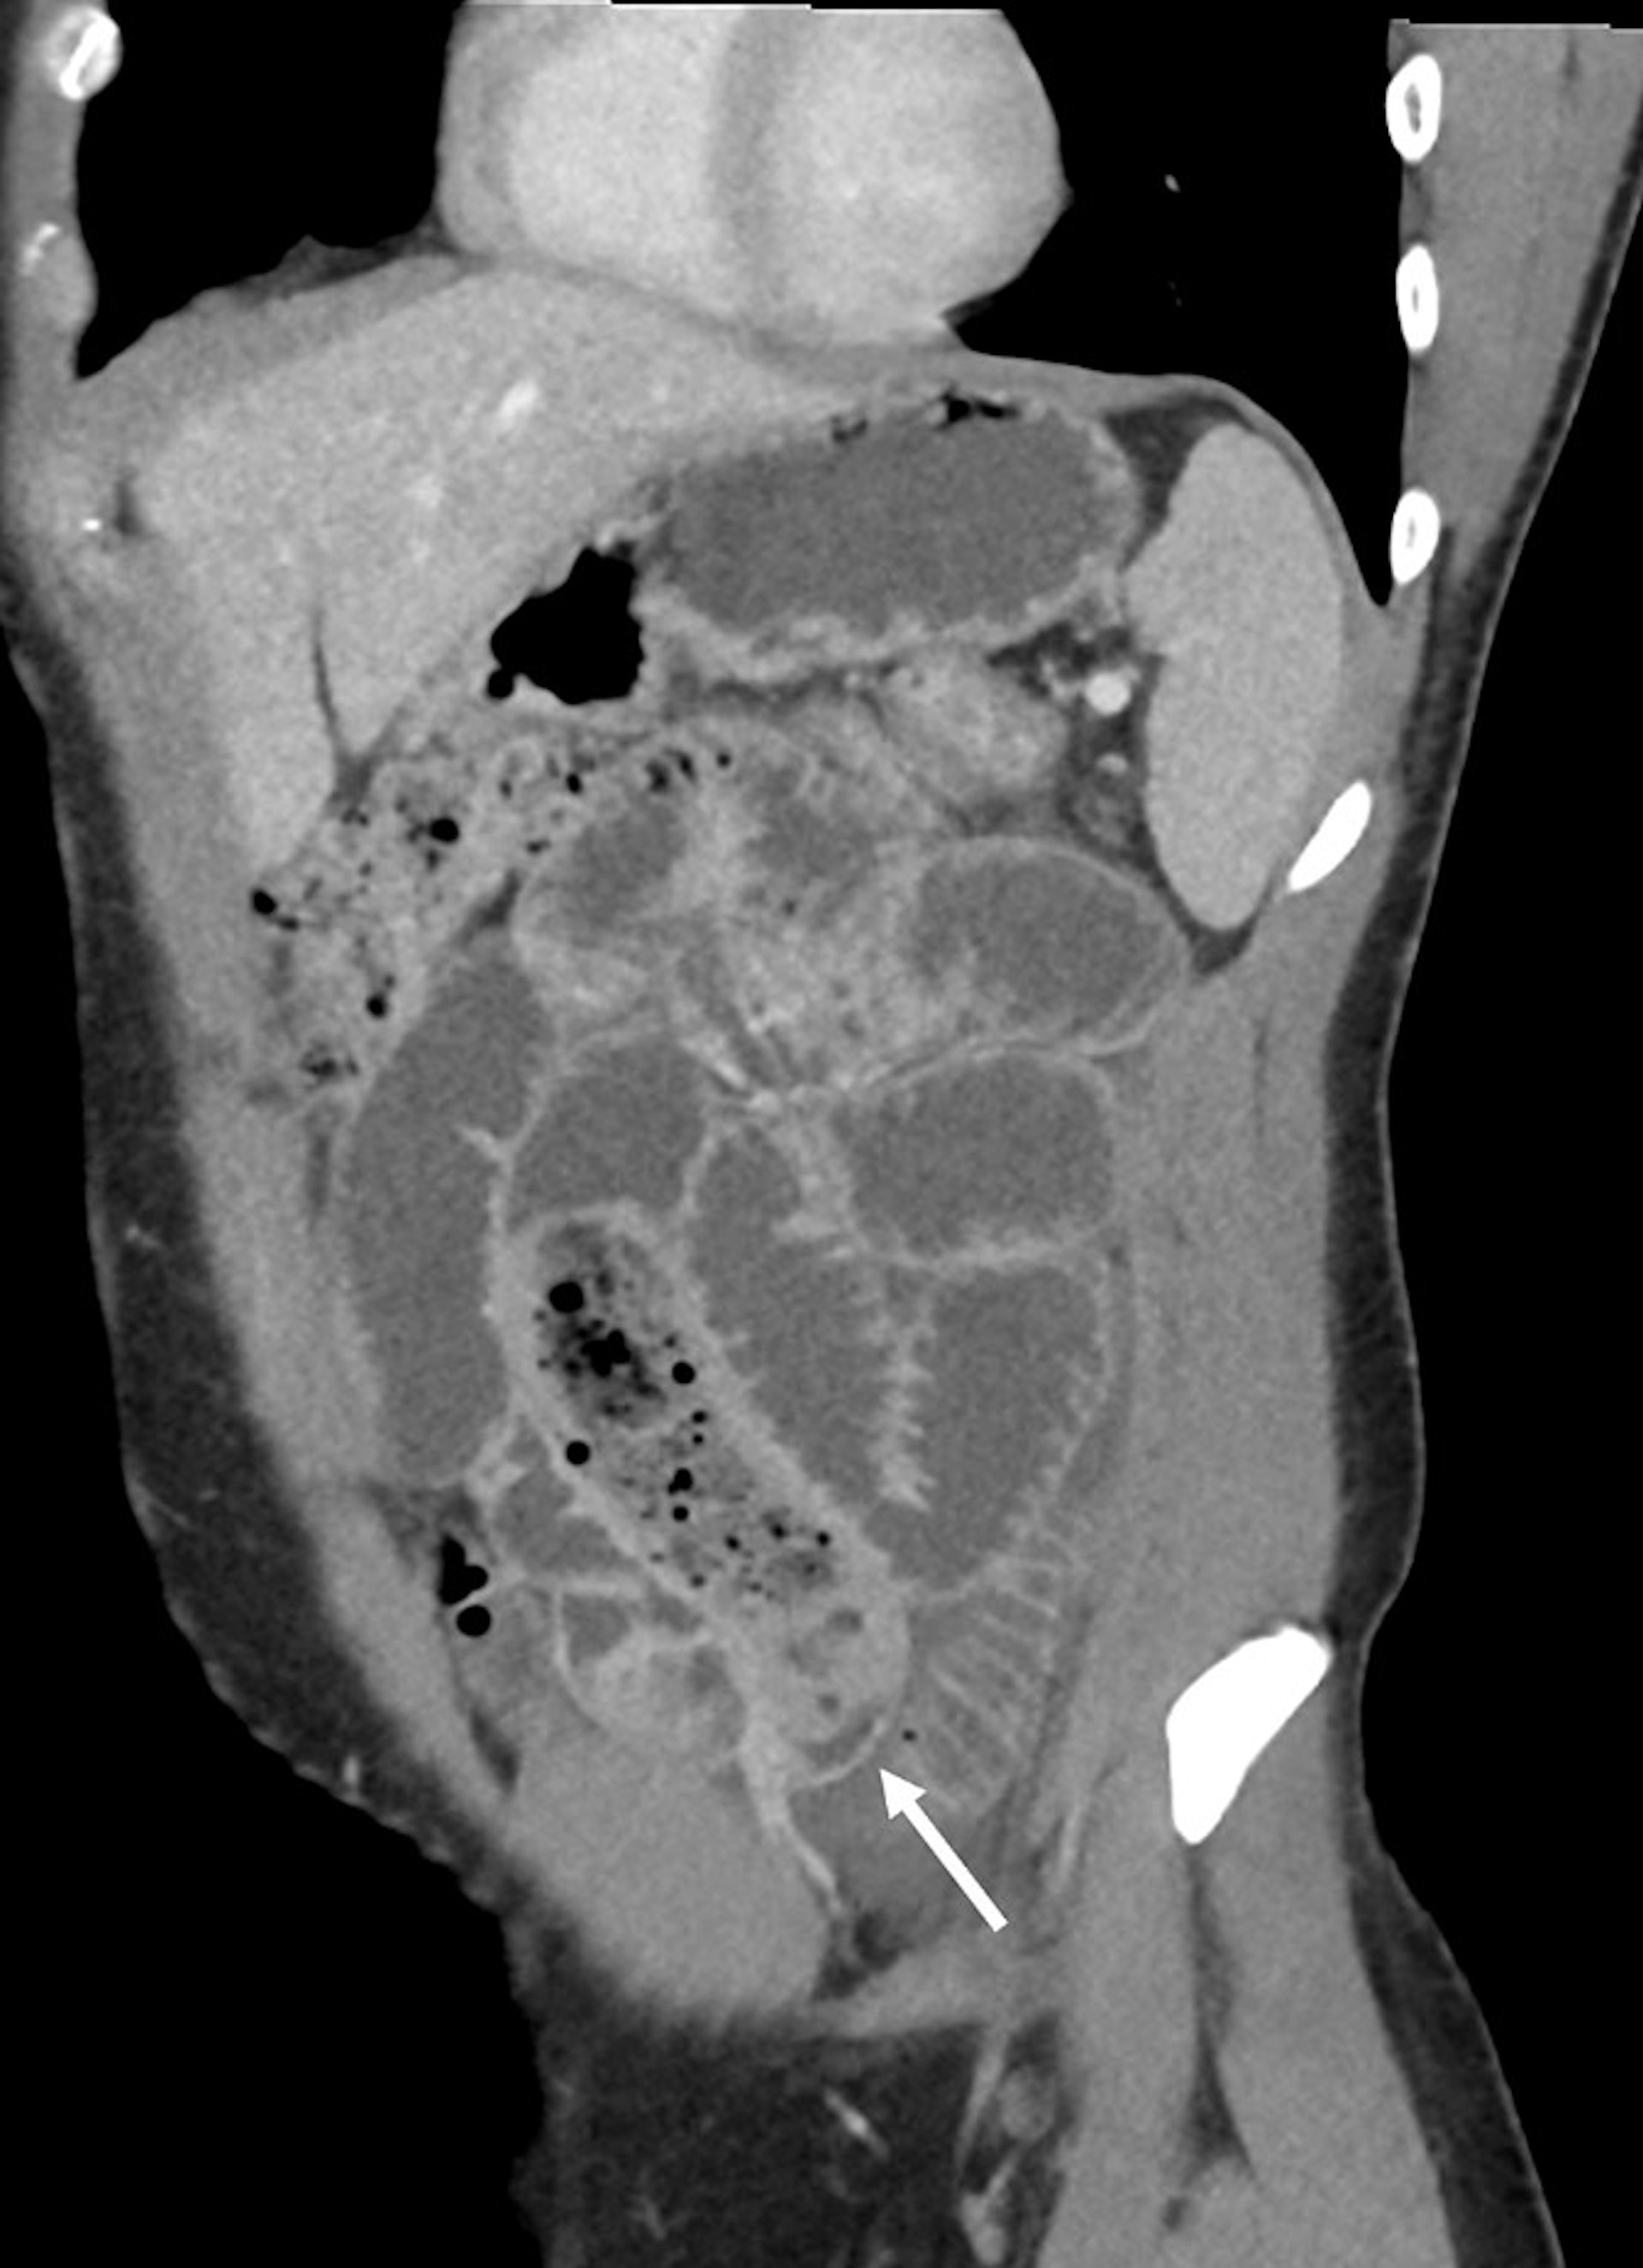

醫生為男子進行電腦斷層掃瞄,顯示他的腸內有明顯的長條狀異物。(「Cureus」圖片)

醫生為男子進行電腦斷層掃瞄,顯示他的腸內有明顯的長條狀異物,而小腸擴張達3.5 cm並伴有糞便。考慮到男子小腸梗阻的嚴重程度,醫生不採取保守治療等待排出,而是緊急透過手術取出異物。從術後拍攝的照片可見,香蕉已經發黑軟爛滲液,而安全套被打了結因此內容物沒有流出。